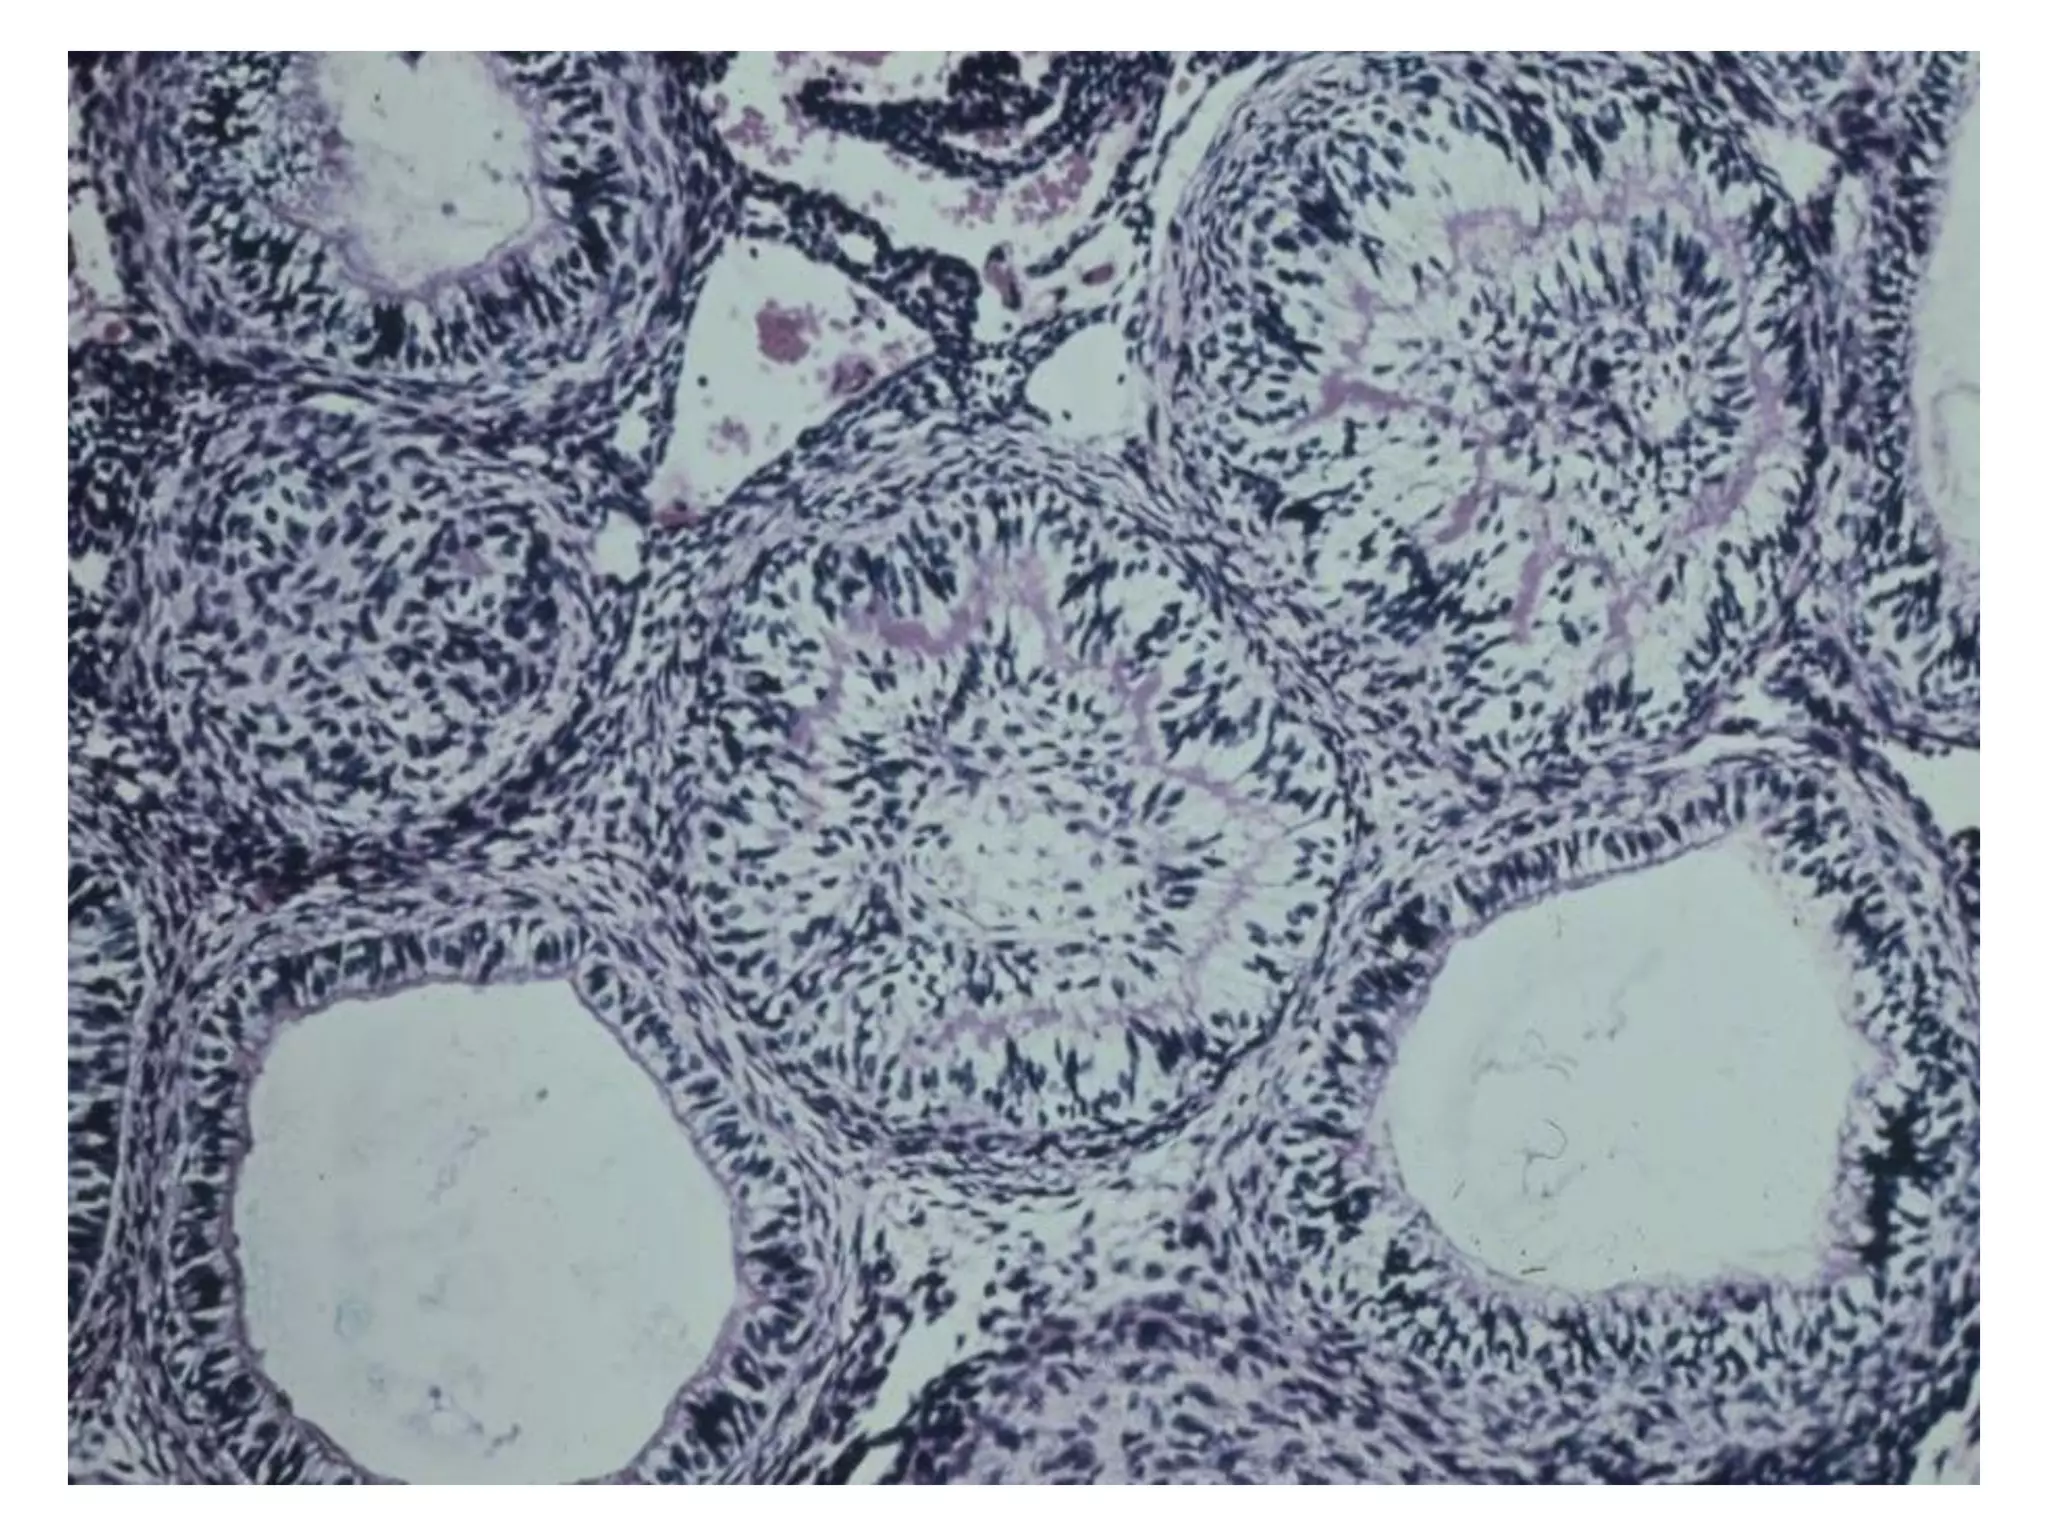

Ameloblastoma: daïng ñaëc hay ña

nang

Giaûi phaãu beänh

 Coù nhieàu döôùi típ (subtypes) treân vi theå nhöng

chuùng thöôøng mang ít ñaëc tính cuûa khoái u.

 Thöôøng gaëp nhaát laø daïng nang (follicular type) vaø

daïng ñaùm roái (plexiform type).

 U men ñaëc daïng nang goàm caùc ñaûo teá baøo bieåu moâ

gioáng cô quan men naèm trong moâ lieân keát sôïi tröôûng

thaønh.

 U men ñaëc daïng ñaùm roái goàm caùc daây (cords) bieåu

moâ taïo raêng daøi thoâng nhau hoaëc caùc laù (sheets)

bieåu moâ lôùn hôn. Moâ ñeäm loûng leõo vaø nhieàu maïch

maùu hôn.

follicular type